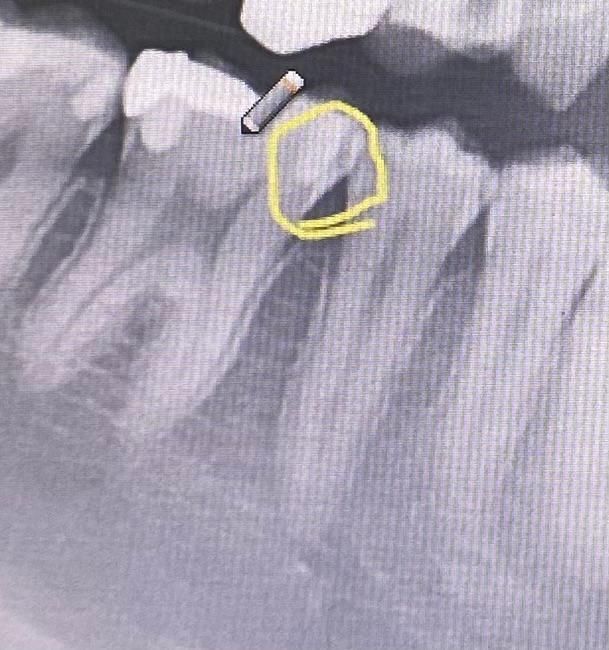

충치 치료 여부가 궁금합니다. 알고싶습니다.

이 부분 충치치료가 반드시 필요할까요?

아니면 양치질해보면서 지켜보는게 좋을까요 ?

치과 2곳을 갓는데 한곳은 치료하자하고 한곳은 지켜보자고 하십니다 ㅠㅠ

혹시 하얀색으로 된 부분 까지 썩은건가요????

• 1번 째 사진

사진이 좀 애매하긴합니다. 작은 사진을 찍어보면 조금 더 정확히 알 수 있겠습니다만 노란동그라미 안쪽 하얀 것은 예전에 때운 것으로 보이고 그 주변이 살짝 검긴한데 다른 방사선사진과 시진으로 평가해봐야할 것 같습니다.